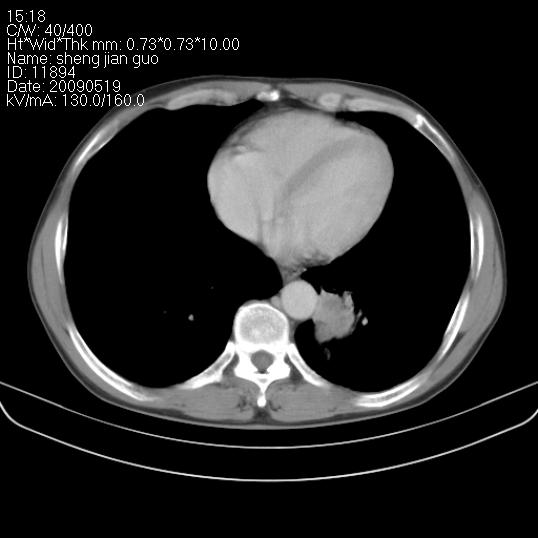

以下是引用zjzjr在2009-5-19 17:25:00的发言:[br]支持楼主考虑,另左肺下叶阻塞性炎症。

以下是引用zhao_bin2008在2009-5-19 17:48:00的发言:[br]支持左肺下叶周围型肺癌并阻塞性肺炎。

以下是引用zsl6918在2009-5-20 7:10:00的发言:[br]左侧中心型肺癌!